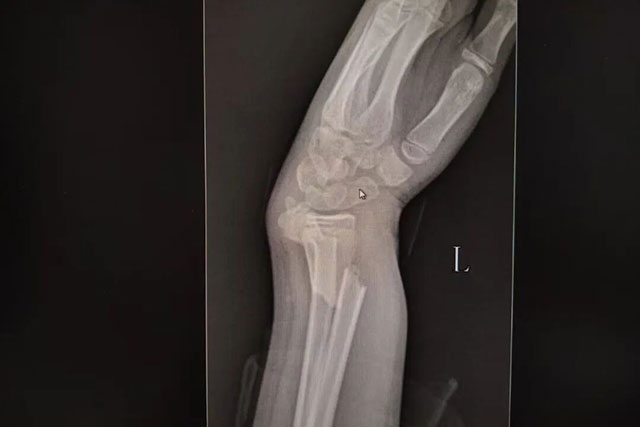

9岁的西安女孩小晗玩耍时意外摔倒,左手前臂以不自然角度扭曲。紧急送医后,X光片显示其尺桡骨双骨折,断端已移位。父母带她辗转当地多家医院,均建议手术复位。

次日,一家人跨越千里赶到正骨病房。此时付至江主治中医师刚结束治疗,便立刻接过病历和片子。他细细比对后,轻触小晗前臂检查,动作轻柔:“孩子骨骼柔韧,尺桡骨双骨折,首选中医正骨保守治疗……”

复查X光片显示,骨折断端复位良好。夕阳洒进病房,落在小晗的夹板上,也照亮一家人的笑脸。妈妈轻抚女儿的头:“这趟没白来,中医正骨太神奇了。”